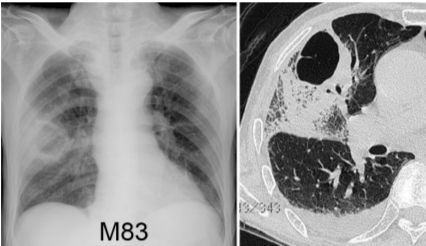

9. 男性,83歲,有吸煙史,因發燒、咳嗽有痰來診,胸部X光和斷層如圖所示,其最可能診斷為何? (A) 空洞性肺癌併阻塞性肺炎 (B) 肺炎併肺膿瘍 ( abscess ) (C) 肺炎併氣囊 ( pneumatocele ) (D) 肺囊腫 ( lung cyst ) 併肺炎 (E) 肺結核